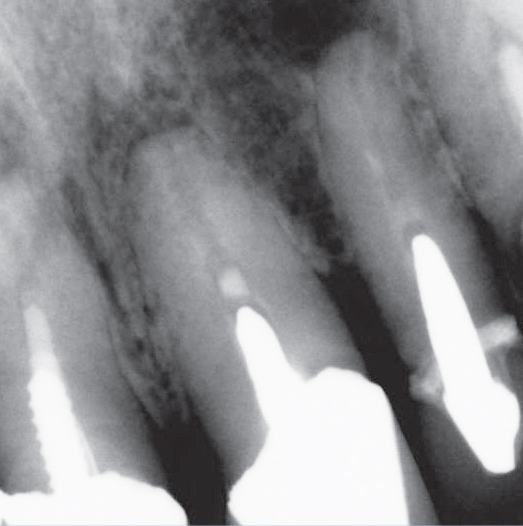

Before

Before Root Canal treatment